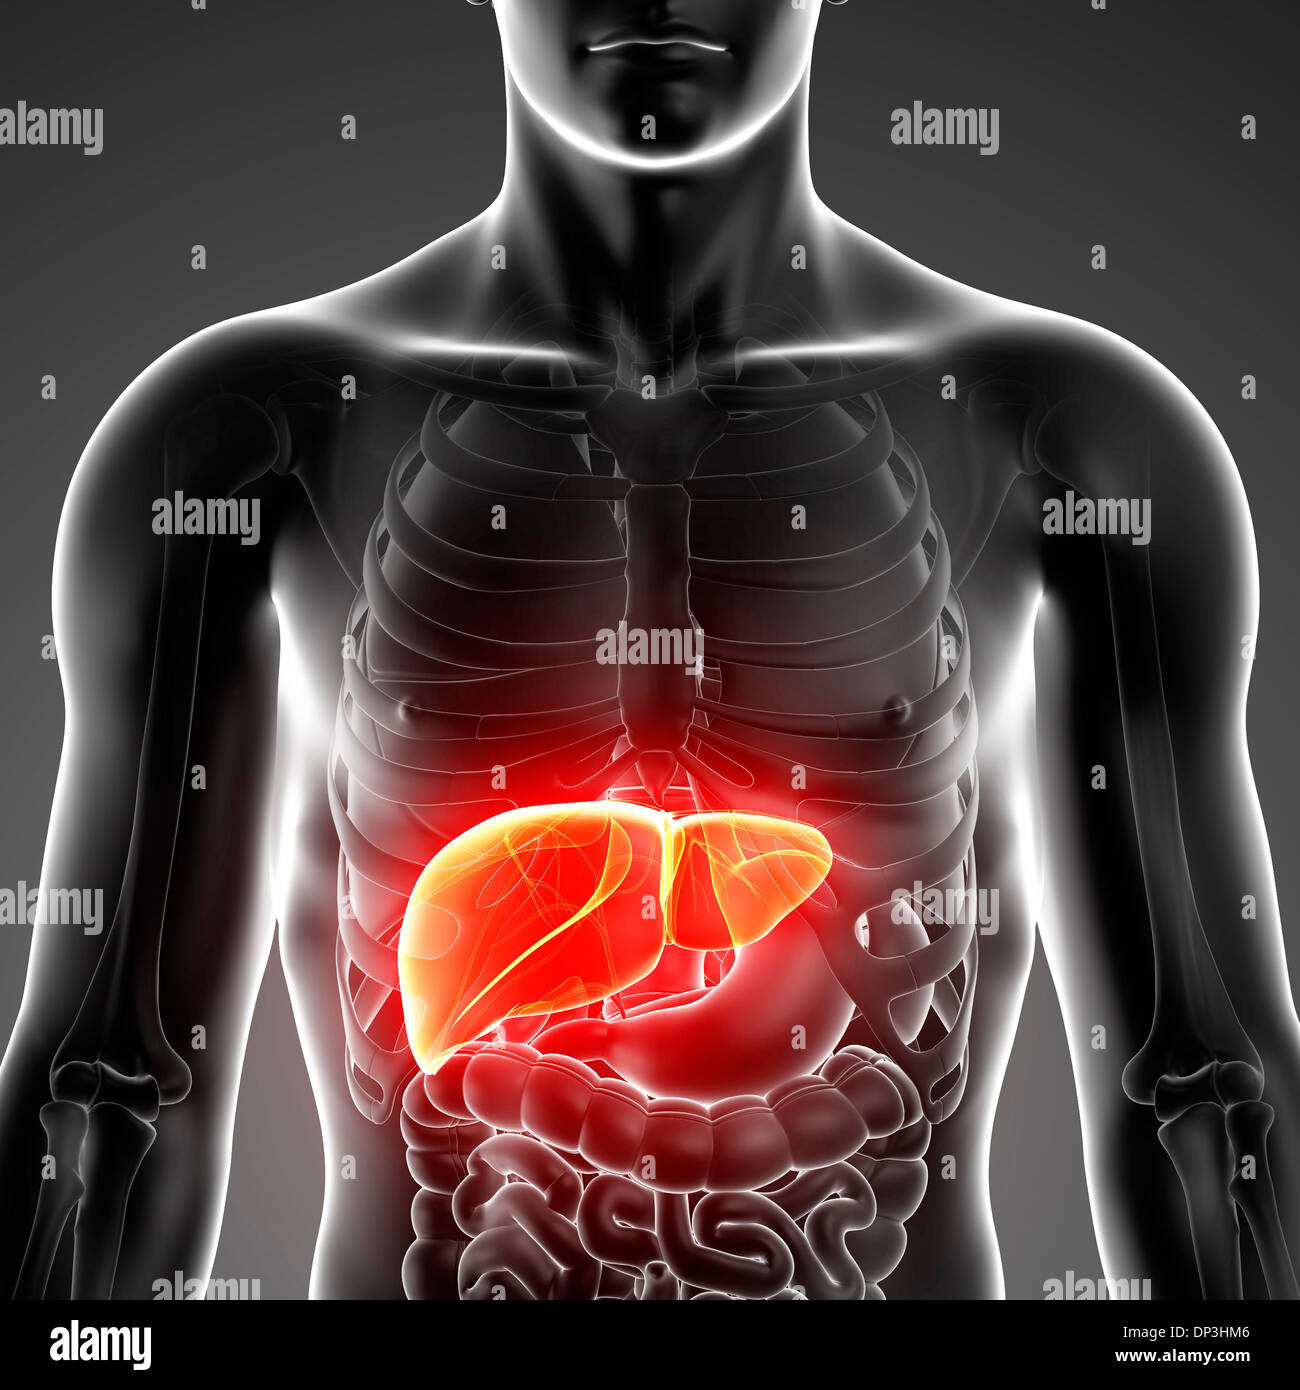

RFPAYTH0–Innere Organe, männlichen Körper - schematische Darstellung der menschlichen Anatomie Illustration - auf weißem Hintergrund.

RFDGYRD7–Männliche Anatomie, inneren Organe allein, volle Atmungs- und Verdauungssystem, mit einigen Organen Cutaway. Anatomie-Bild.